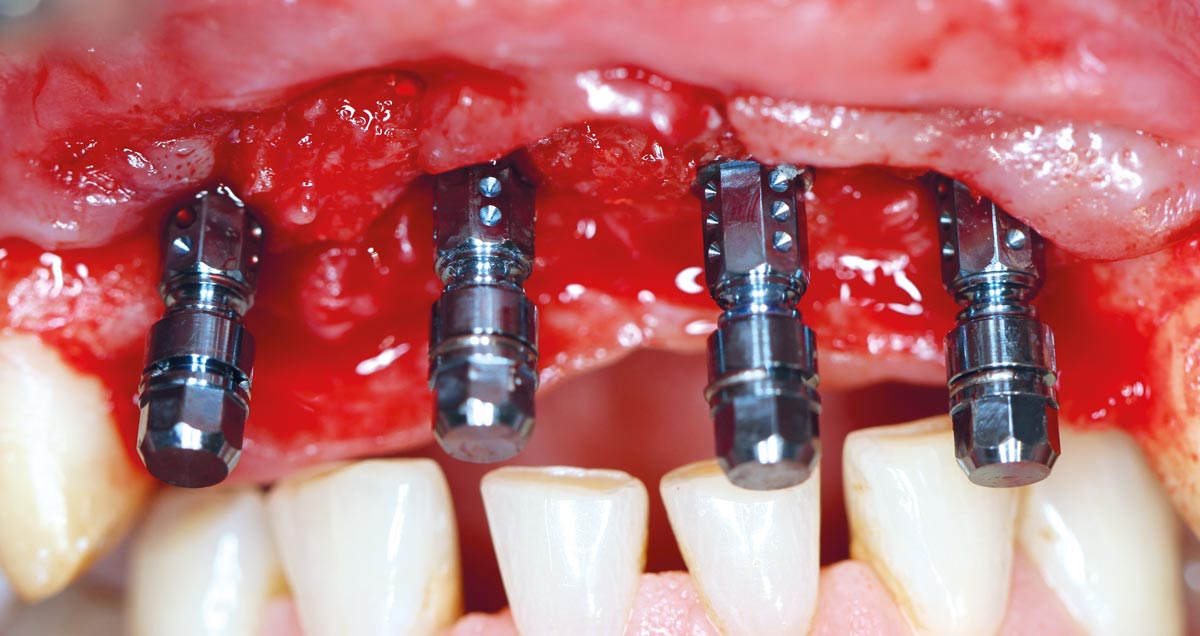

11/17 - Four implants were inserted (Straumann Bone Level Roxolid®)Restoration of all four incisors with maxgraft® bonebuilder - Dr. Dr. Dr. O. Blume